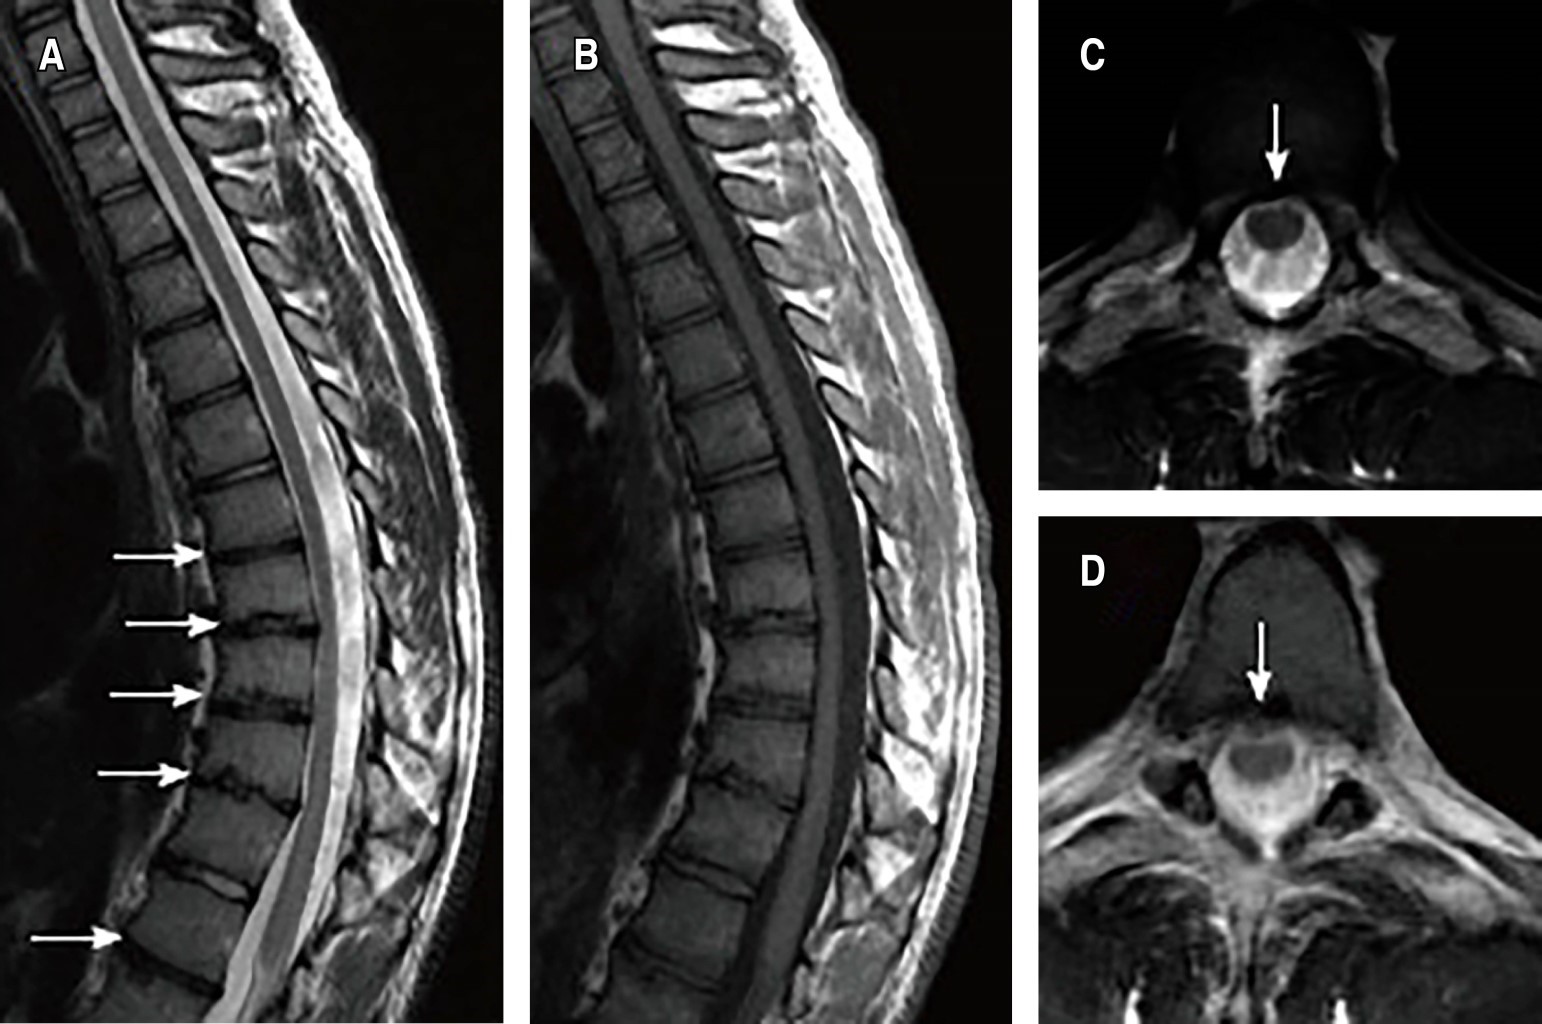

Hallazgos en la resonancia magnética. Aquellos pacientes que presenten déficit motor o sensitivo, hiperreflexia u otras alteraciones en la exploración neurológica, o en caso de planificación quirúrgica, se debe completar el estudio por imagen mediante resonancia magnética (RM) para descartar la presencia de herniación discal, tracción o compresión medular en el ápex de la deformidad. Incluyen platillos vertebrales irregulares, nódulos de Schmorl (16-35%), afectación discal (50%), espondilosis/espondilolistesis, edema óseo (que suele asociarse a dolor espalda) y/o escoliosis (Figura 4).12,13